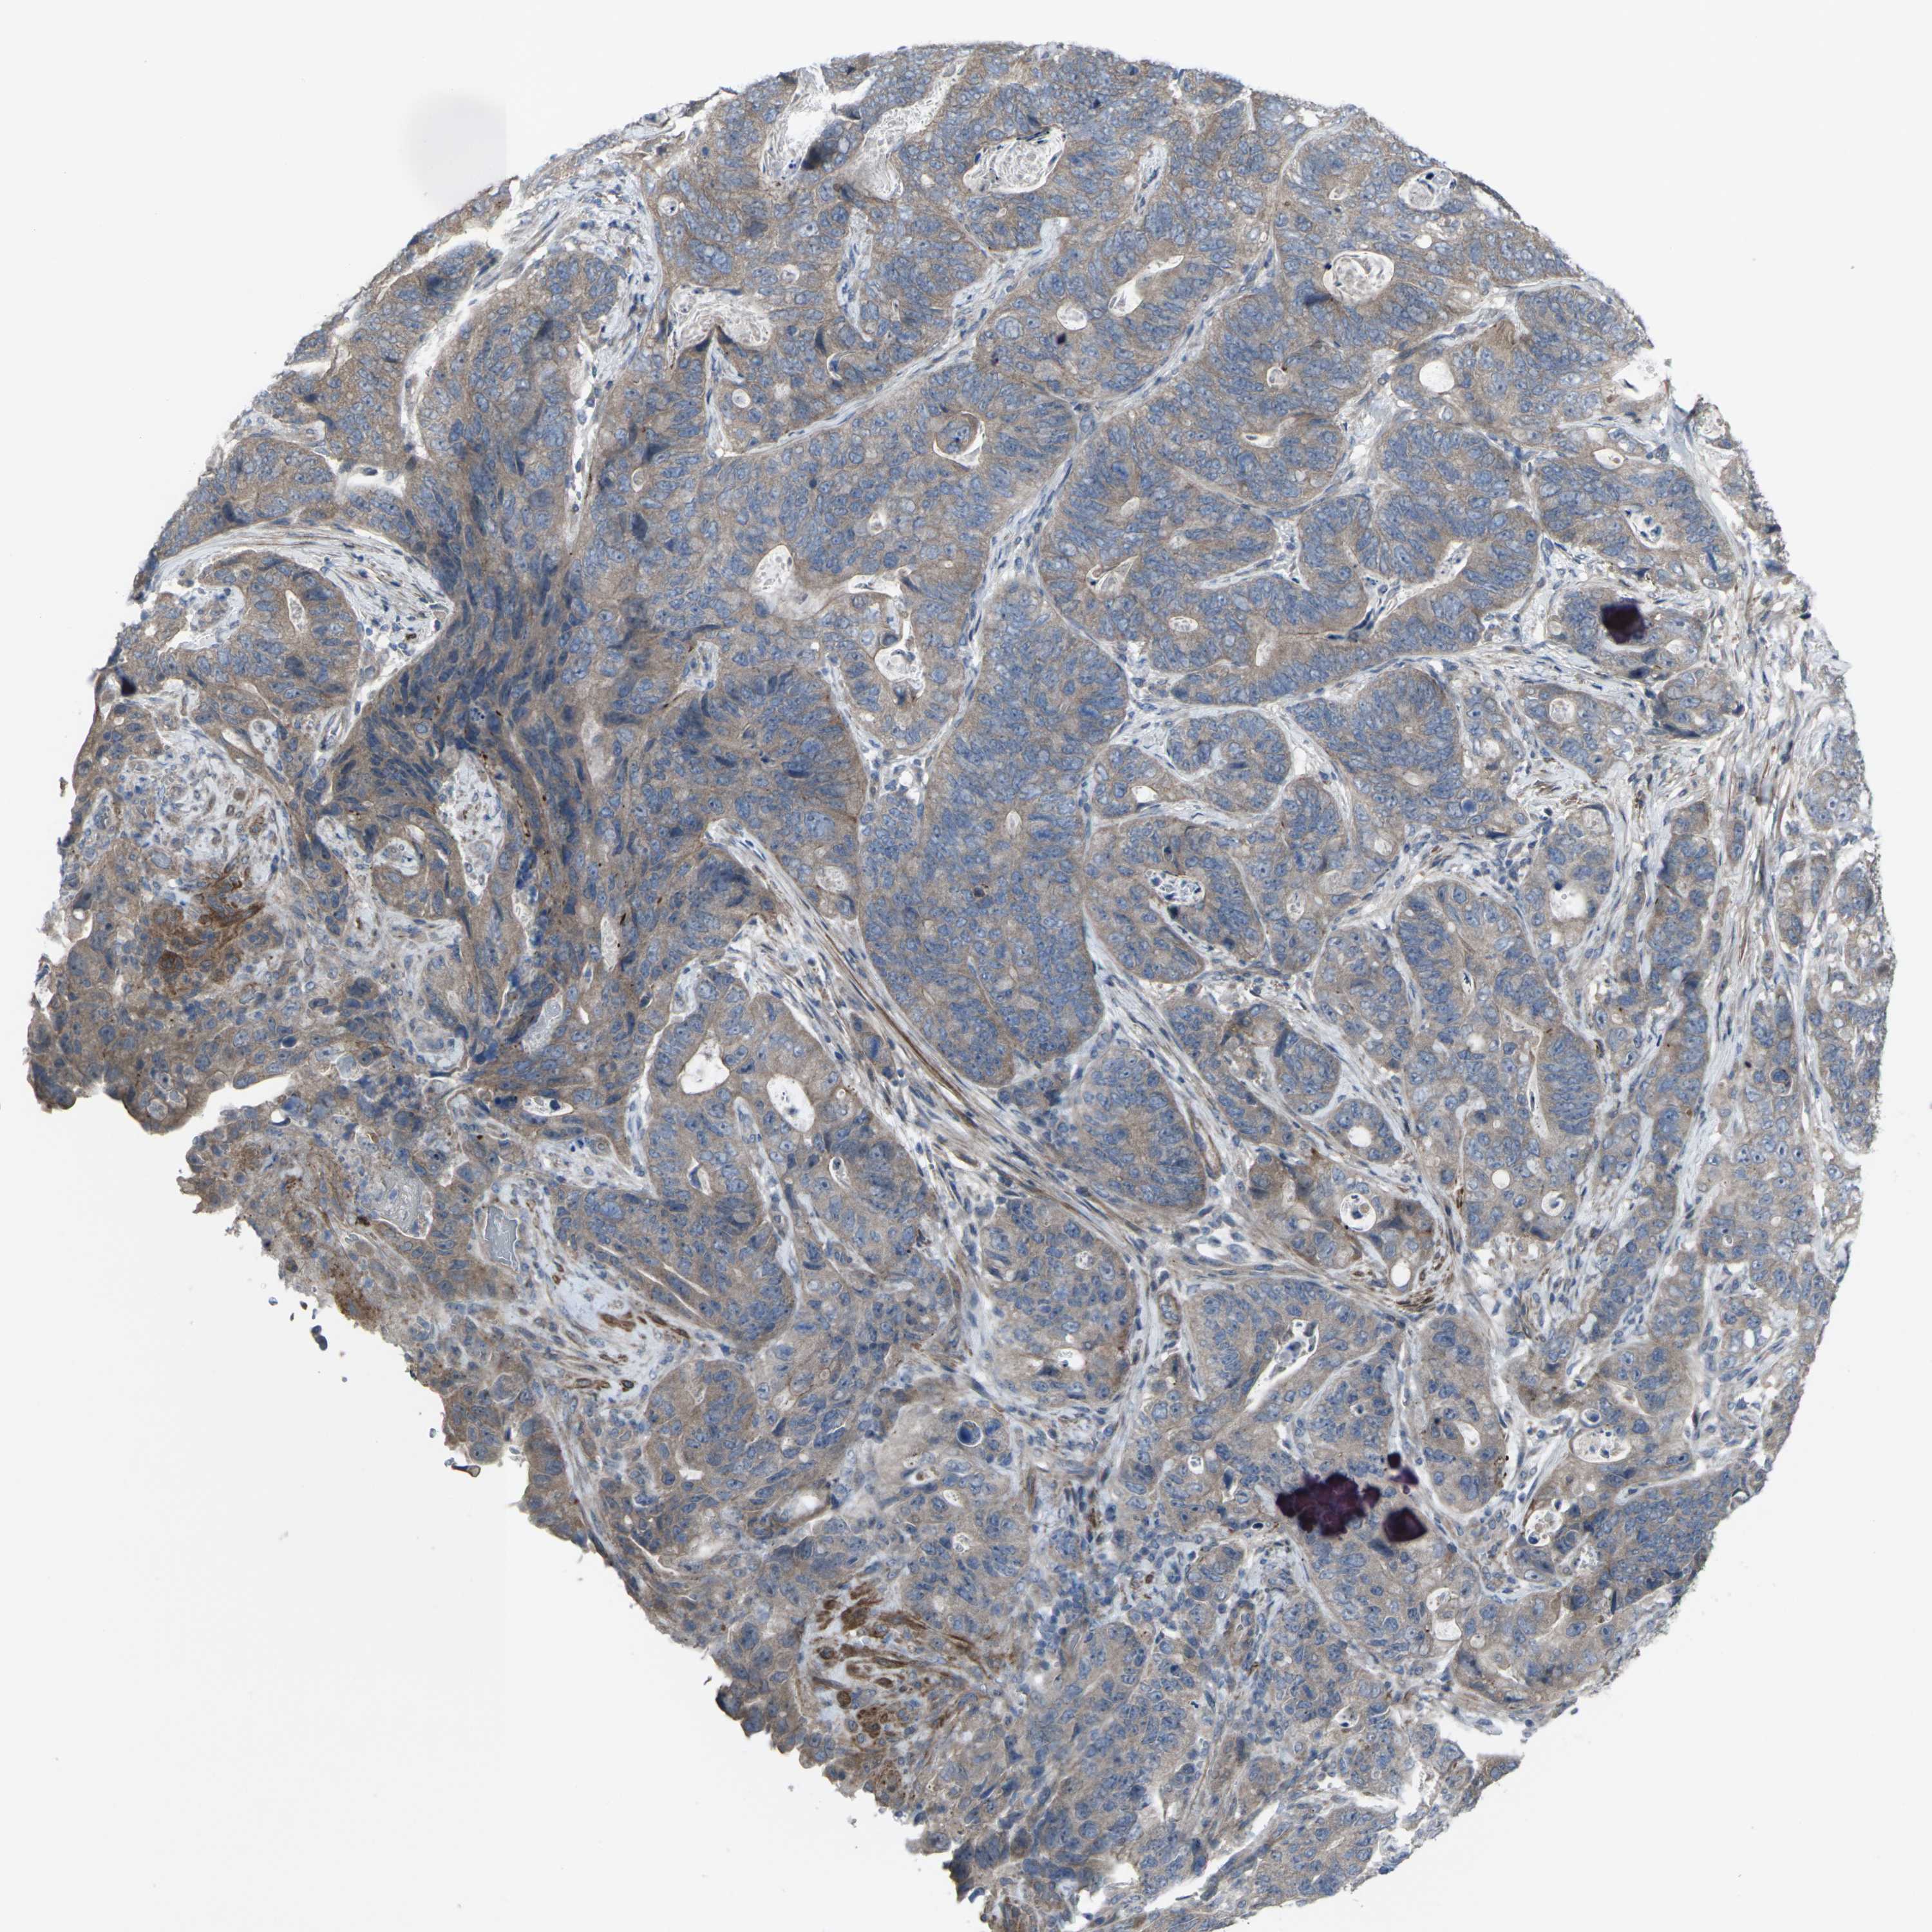

STOMACH CANCER - Protein expressioni

A mouse-over function shows sample information and annotation data. Click on an image to view it in a full screen mode. Samples can be filtered based on level of antibody staining by selecting one or several of the following categories: high, medium, low and not detected. The assay and annotation is described here.

Antibody stainingi

Antibody staining in the annotated cell types in the current human tissue is reported as not detected, low, medium, or high, based on conventional immunohistochemistry profiling in selected tissues. This score is based on the combination of the staining intensity and fraction of stained cells.

Each image is clickable and will lead to virtual microscopy that enables deeper exploration of all samples and also displays staining intensity scores, fraction scores and subcellular localization as well as patient and tissue information for each sample.

Antibody CAB011684

Staining

High

Medium

Low

Not detected

Intensity

Strong

Moderate

Weak

Negative

Quantity

>75%

75%-25%

<25%

None

Location

Nuclear

Cytoplasmic/membranous

Cytoplasmic/membranous,nuclear

Adenocarcinoma, NOS

Adenocarcinoma, High grade